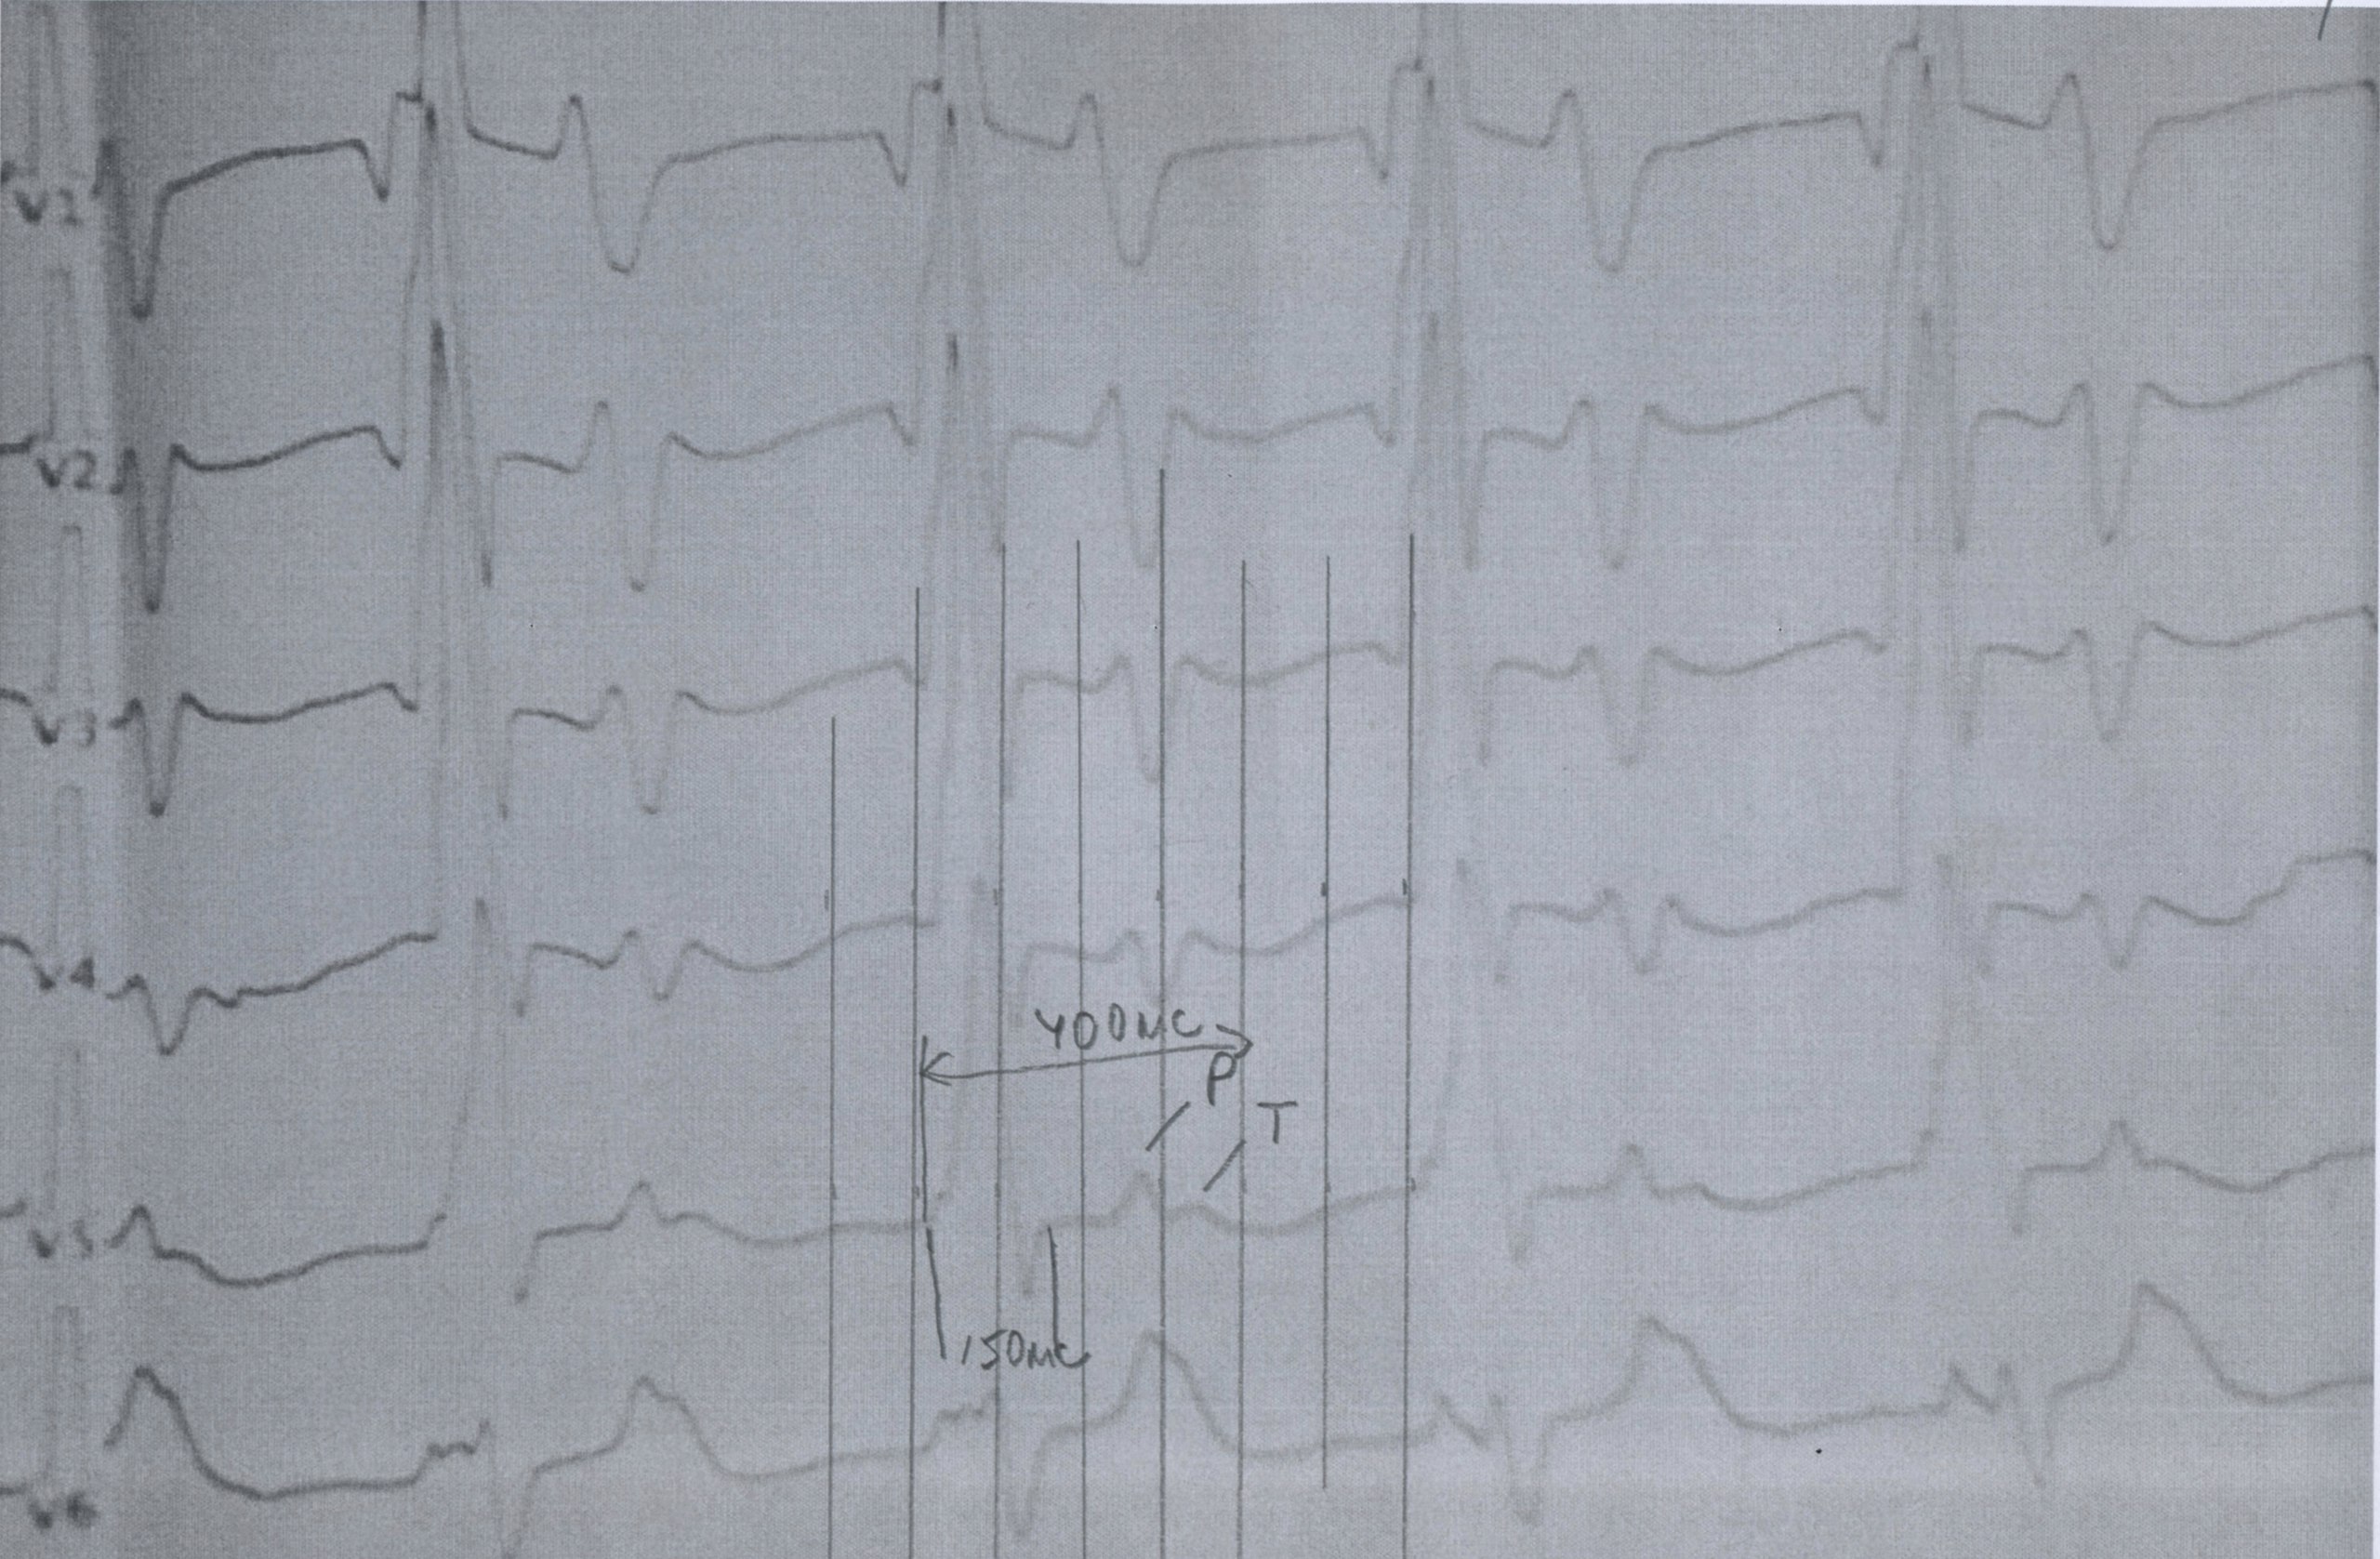

Анамнез - аномальное отхождение магистральных сосудов, сосуды из одного желудочка. Порок не коррегированный

Ритм АВ узла

Аортальный стеноз